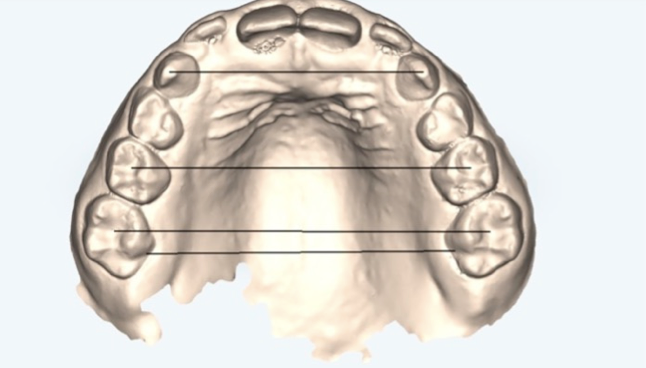

De hecho, el artículo nos habla de un aspecto especialmente interesante: el “efecto bowing” que encuentran en uno de los papers analizados.

Básicamente, mientras la curva de Spee no esté plana, no deberíamos intruir los incisivos.

Eso suele requerir proinclinación y en determinados casos un compromiso periodontal intratratamiento… pero es importante que tengamos en cuenta que sin esto la intrusión no se expresará.